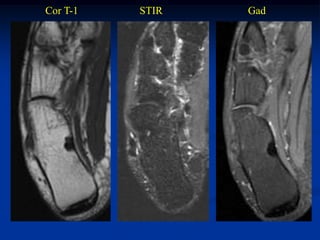

Case #1168.1                        Bone island

Bone scan

55 year male with workup for possible bone metastasis

Cor T-1   STIR   Gad